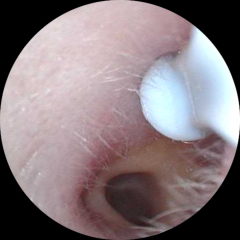

bananaphon · 05/07/2024 07:36

Update pics! The last one was taken this morning. My ear drum is no longer blocked which is such a relief. This was just by using olive oil drops on the 2 occasions and the wax has slowly softened and come out in the last week. Since last night and I can actually hear properly for the first time since May!

Used my ear camera

OP posts: